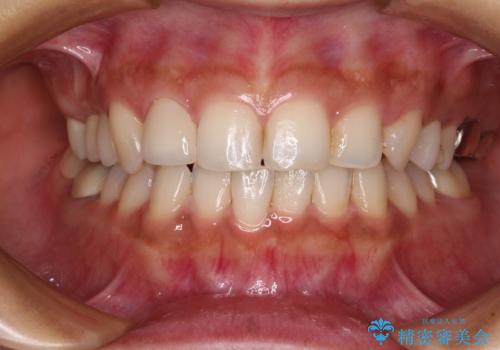

- 冷たいものがしみたり、ものが挟まったり、噛んだときに痛んだりするとのことで来院された患者様です。

治療開始時は右上奥歯と前歯のみが気になっていたのですが、その後下顎左右の奥歯に強い痛みや銀歯の脱離などが頻発し、問題のあるところは全て治療を行うこととしました。